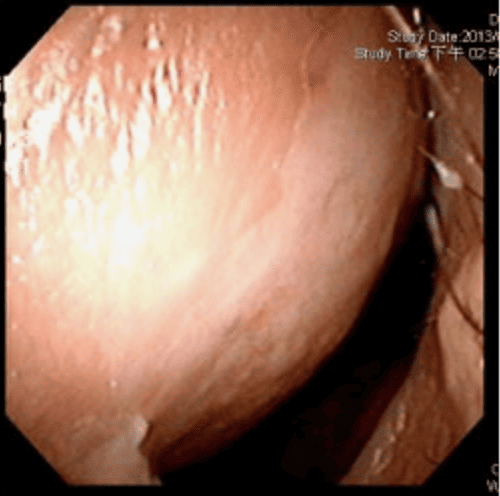

透過內視鏡檢查時,發現F先生右側尾端鼻中隔彎曲,幾乎貼近側壁,而且右側鼻阻力圖呈水平,代表F先生右側鼻空肌膚不能呼吸。鼻中隔軟骨扭曲變形、左上側軟骨凹陷萎縮,我們團隊先進行鼻部結構拆解及鼻中隔成形手術,再利用取下的鼻中隔軟骨進行重建,同時進行右側截骨術(Osteotomy),從根本矯正歪斜的鼻樑。